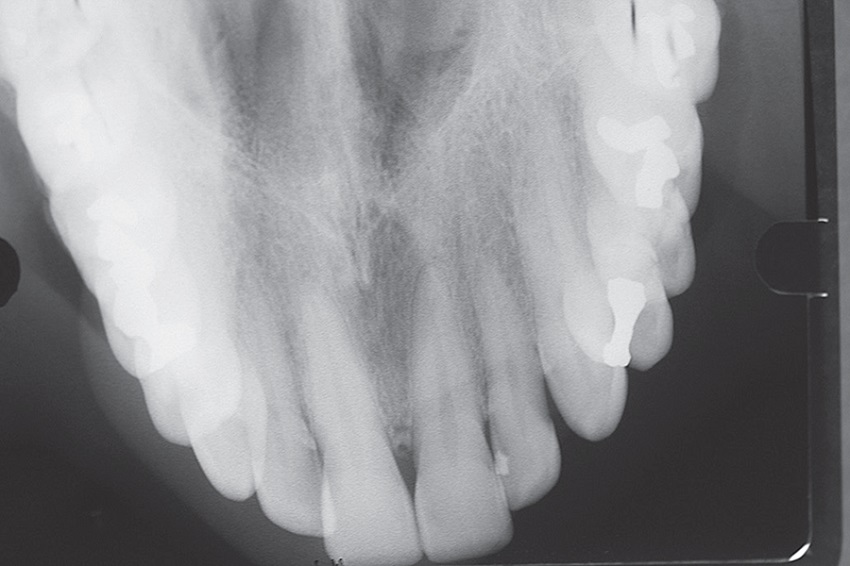

A 62-year-old male patient, Caucasian, sought the Stomatology Clinic of the Department of Dentistry of the Pontifícia Universidade Católica de Minas Gerais (PUC Minas) complaining of swelling in the anterior region of the palate. He reported realizing the condition 40 days before, which was continuously growing and painful to touch and when chewing. The anamnesis did not reveal systemic alterations. At extraoral examination, no alterations were observed. The intraoral examination showed a soft texture swelling, slightly purplish in color, with increased in translucency, suggestive of fluid content, covered by an intact mucosa, located on the anterior hard palate in the midline, close to the incisive papilla, measuring approximately 1.5 cm in diameter (Figure 1). Periapical and occlusal maxillary radiographs showed a well-defined unilocular radiolucent area in the incisive foramen region (Figure 2). Cone Beam computed tomography (CT) examination was requested to better evaluate the limits of the lesion, which showed a well-defined hypodense area, in continuity with the incisor canal, measuring 15 × 13 mm, in transversal and axial sections (Figure 3). Pulp vitality tests were performed on upper incisor teeth with a positive result for all of them. Based on the clinical and imaging characteristics, the diagnostic hypothesis of nasopalatine duct cyst was established, and the proposed treatment was surgical removal of the lesion. Under local anesthesia, aspiration of the lesion fluid was performed, which revealed the presence of translucent fluid. Subsequently, an intrasulcular incision and detachment of the palatal mucosa were performed in the region between the maxillary right and left first premolars (Figure 4). After exposure of the lesion, we performed dissection between the cystic capsule and the mucosa, which were adhered, followed by cyst enucleation and cleaning the surgical cavity (Figure 5). The mucoperiosteal flap was then repositioned and sutured.